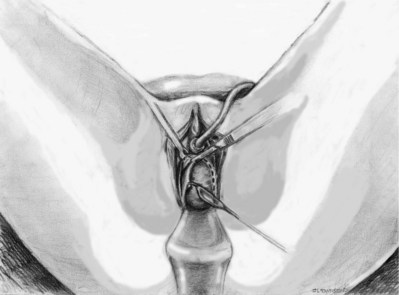

Stamey needles or large clamps are passed from above, through the abdominal incision by careful guidance behind the pubis, and passage is in contact with the pubis throughout until brought out lateral to the bladder and through the vagina (Fig. 73–5). Alternatively, large surgical instruments such as Tonsil clamps may also be used (McGuire, 1978; Blaivas and Olsson, 1988). The bladder must be completely drained before passage of the Stamey needles to avoid inadvertent bladder injury. Cystoscopy should be performed with a 70-degree lens after passage of the needles to confirm the integrity of the bladder, by following the course of the needles (while an assistant moves them). Cystoscopy is not practiced consistently by all urologists after needle passage except when there is visible hematuria or another cause for suspicion (Niknejad et al, 2002; Seung-June et al, 2007). It is the authors’ belief that this step eliminates the morbidity and reoperation required for passage of the sling through the bladder and that cystoscopy is an essential step. In the case of a small bladder injury or inadvertent passage of Stamey needles through the bladder, the needles are removed and passed again and the procedure is completed. Extravesical passage is confirmed. One ampule of indigo carmine is given at this point to confirm ureteral efflux during final cystoscopy for tensioning of sling. The Foley catheter is replaced. The ends of graft suture are passed through the Stamey needle eyelets. After marking the center of the graft with a clamp, the Stamey needles are removed and the ends of the suture are brought out through the abdominal incision and tagged with hemostat clamps (Figs. 73-6 and 73-7). The distal aspect of the graft is sutured to the periurethral tissue with two simple 4-0 polyglactin sutures. The vaginal incision is closed with a watertight, running 2-0 polyglactin suture after complete hemostasis is achieved. Before final tensioning of the sling (see Fig. 73-7) the vagina should be closed and the weighted speculum removed to eliminate factors that can affect the final tension. The polydioxanone sutures are tied down above the rectus fascia (see Fig. 73–7) while cystoscopy with a 30-degree lens is performed to visualize adequate coaptation of the proximal urethra. There is approximately a two-fingerbreadth width between the rectus fascia and the sutures once tied down. The amount of tension may vary owing to the mobility of the urethra or desire to create permanent retention in an individual who will have permanent catheterization. The abdominal incision is closed with a subcuticular 4-0 polyglactin suture. The Foley catheter is left to straight drainage, and a vaginal pack moistened with conjugated estrogens is placed.